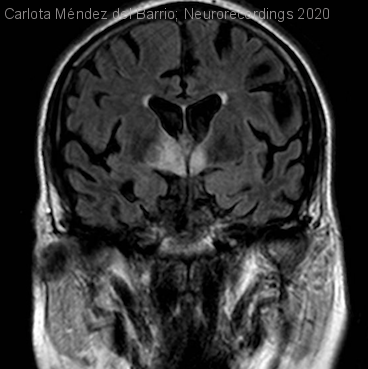

Demencia rápidamente progresiva por enfermedad de Whipple.

Hombre | 64 años

Diagnóstico final: Enfermedad de Whipple

Neurología: Trastornos cognitivos | Infecciosas

Etiología: Infecciosas / inflamatoria / desmielinizante